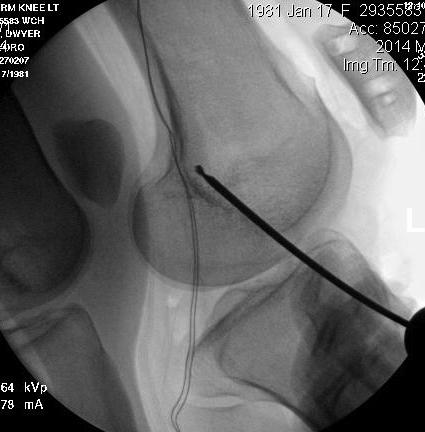

Xrays 1

Tunnel too anterior / tight in flexion